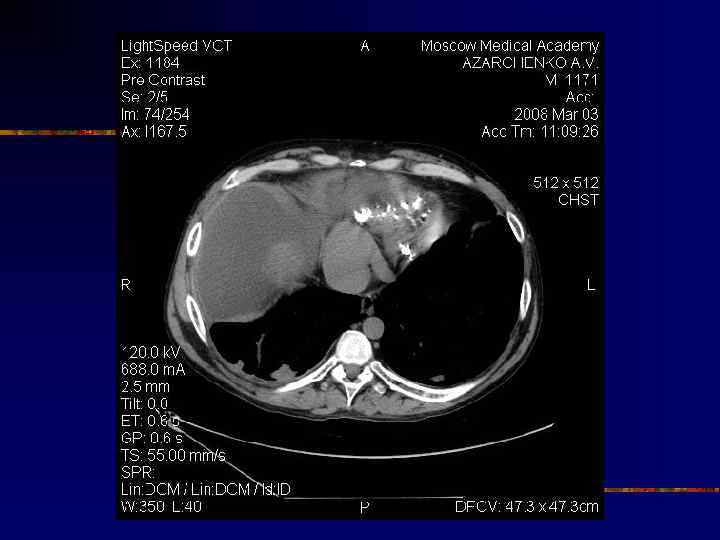

Кальциноз перикарда